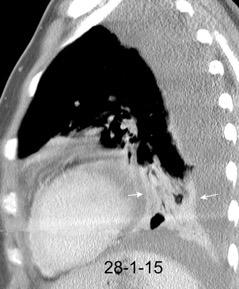

Marzo 2014: Perforación longitudinal distal secundaria a episodio de vómito (síndrome de Boerhaave). Derrame pleural izdo. que evoluciona a empiema.

Wang C-T et al. Tension hydropneumothorax in a Boerhaave syndrome patient: A case report . World J Emerg Med, 2021. Katabathina V et al. Nonvascular, nontraumatic mediastinal emergencies in adults:a comprehensive review of imaging findings. Radiographics. 2011.